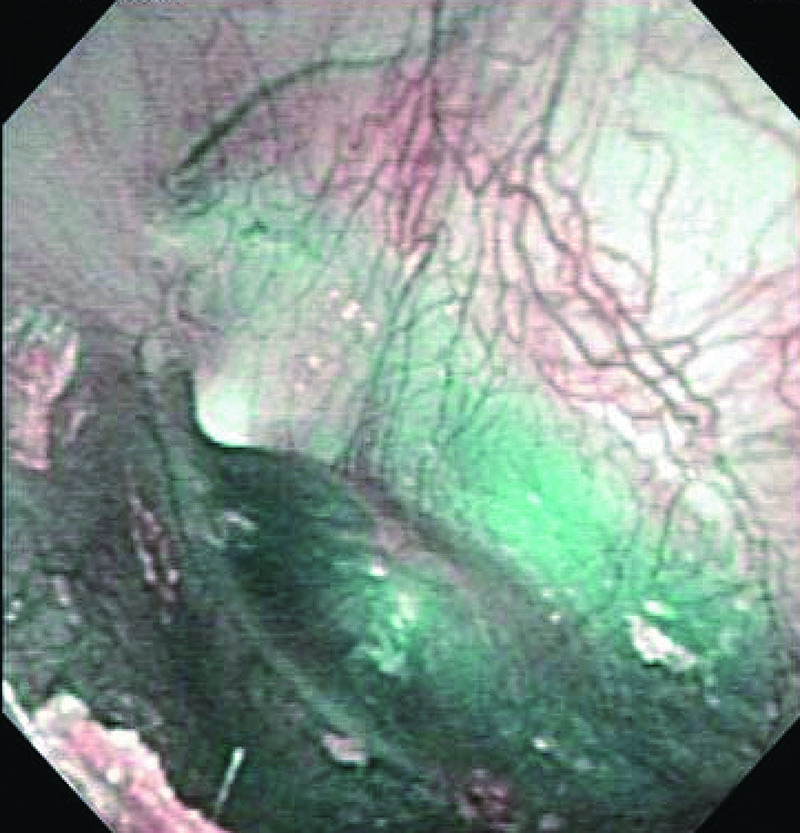

Normal Eardrum

Comment:

With a normal eardrum, NBI can enhance visualization of superficial vessels running from up above along the malleus.

Images and comments by Dr. S. Takano <ENF-V2>